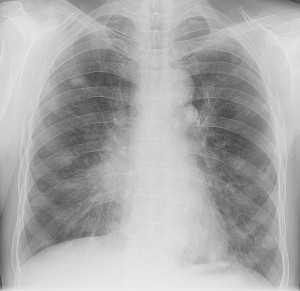

Метастазы в легких — фото рентгенограммы. Округлые тени — метастазы рака пищевода. Хорошо виден большой узел округлой формы вблизи переднего отрезка 2-го ребра. На снимке справа - циркулярное сужение пищевода за счет опухолевого утолщения его слизистой оболочки.

Как выглядят метастазы в легких на рентгене? Слева — узловые образования у пациента с раком яичка. Справа - метастазы рака яичников гематогенного характера с выраженным опухолевым лимфангиитом (обратите внимание на деформированный сетчатый, линейный характер легочного рисунка).

Обратите внимание на увеличение и нарушение структуры корня правого легкого. Это центральный рак. Кроме того, выявлены очаговые тени в обоих легочных полях (гематогенное распространение), а также «лучи», идущие радиально от опухоли корня (лимфогенное распространение).